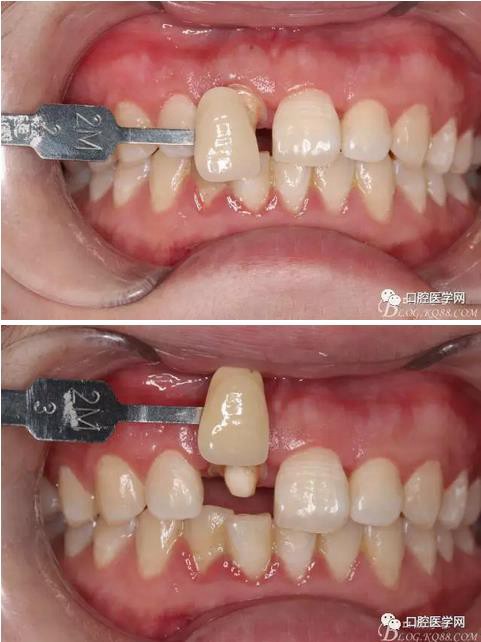

比色

纖維樁+樹脂核

樁道長14mm

備牙